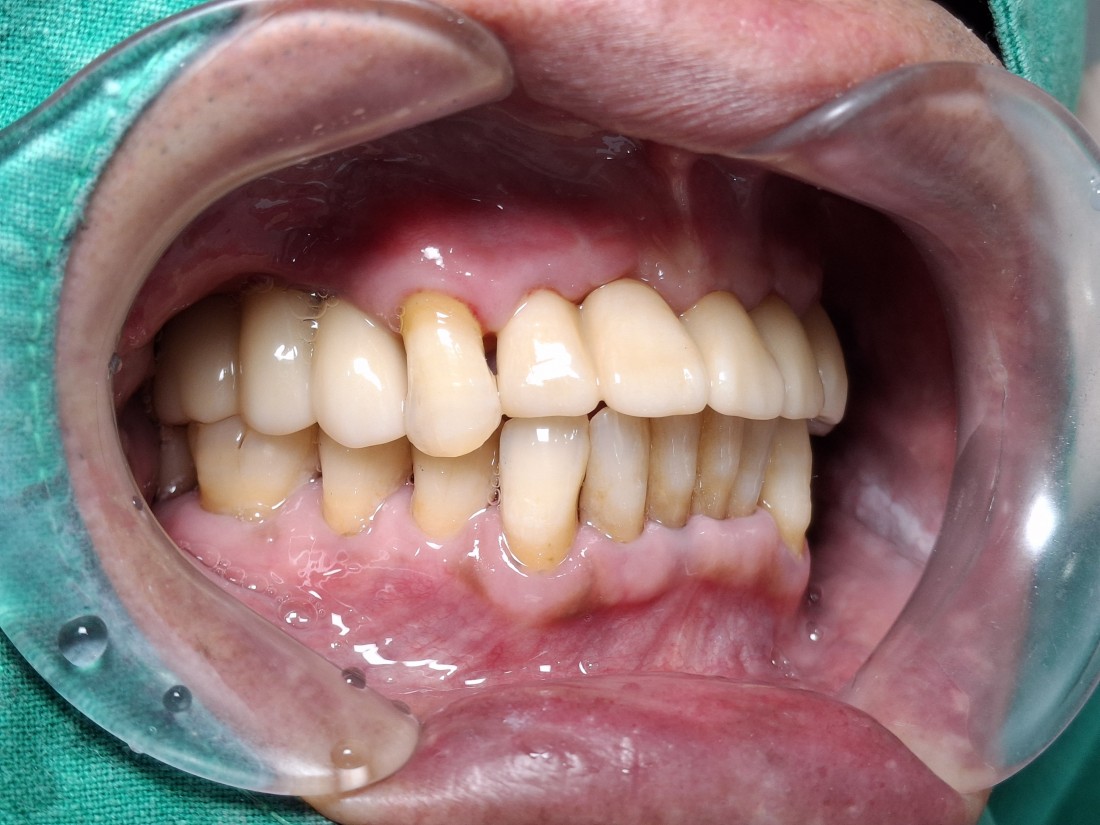

광주 앞니 임플란트,

아직도 오스템만 알고 계시나요?

앞니 임플란트의 성공 비결은

스트라우만 임플란트,

메가젠 블루다이아몬드 임플란트

입니다!

광주 앞니 임플란트 치과에서는

앞니 임플란트 브랜드로

스트라우만이나 메가젠 블루다이아몬드를

많이 추천해드리는데요.

많이 알고계시는 오스템 임플란트와 비교해서

얇은 두께여도 좋은 고정력이 나오기 때문에

앞니 임플란트로 굉장히 적합하기 때문입니다.

광주 앞니임플란트 치과에서

스트라우만 이나 메가젠 블루다이아몬드 로

앞니 임플란트를 진행하면

보통 7일만에 보철물이 올라가며 완성되는데요.

이 일주일 동안 앞니가 없는 채로

일상생활을 해야하는지 많이 걱정하시지만,

발치 후 즉시 임시치아를 부착해드리기 때문에

전혀 문제없이 일상생활을 하시다가

일주일만에 앞니 임플란트 식립을

완성하실 수 있습니다.